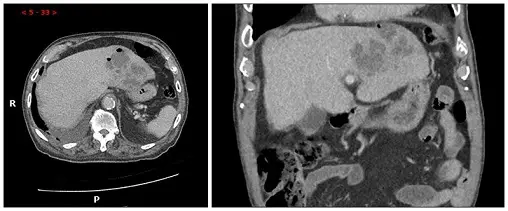

一位50歲糖尿病人主訴右上腹痛、發燒5天來醫院求診,電腦斷層圖示如附圖,下列敘述何者錯誤?

由雙平面對比劑增強電腦斷層(CT)可見右肝葉內有一個大小約數公分的低密度區,周邊可見均勻或不規則的環狀強化(rim enhancement)。冠狀面重組影像亦顯示肝臟深部此囊性病灶,與周邊正常肝實質形成鮮明對比。此影像特徵符合典型的pyogenic abscess:「中心液化壞死」(central necrosis)伴「周邊增強」現象,可見於增生的膿瘍壁及周圍發炎水腫區¹²。影像中未見明顯氣體積聚,亦無明顯多發性病灶或膽道擴張。